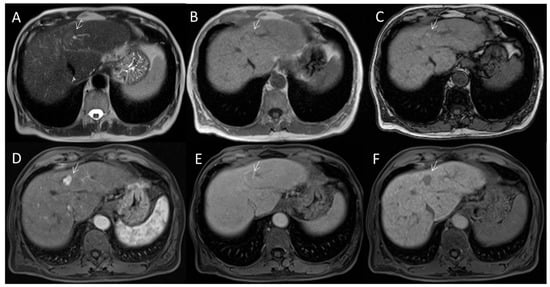

2.2. CT/MRI LI-RADS

2.2.2. CT/MRI Categories

2.2.3. HCC Diagnosis

2.2.4. Ancillary Features